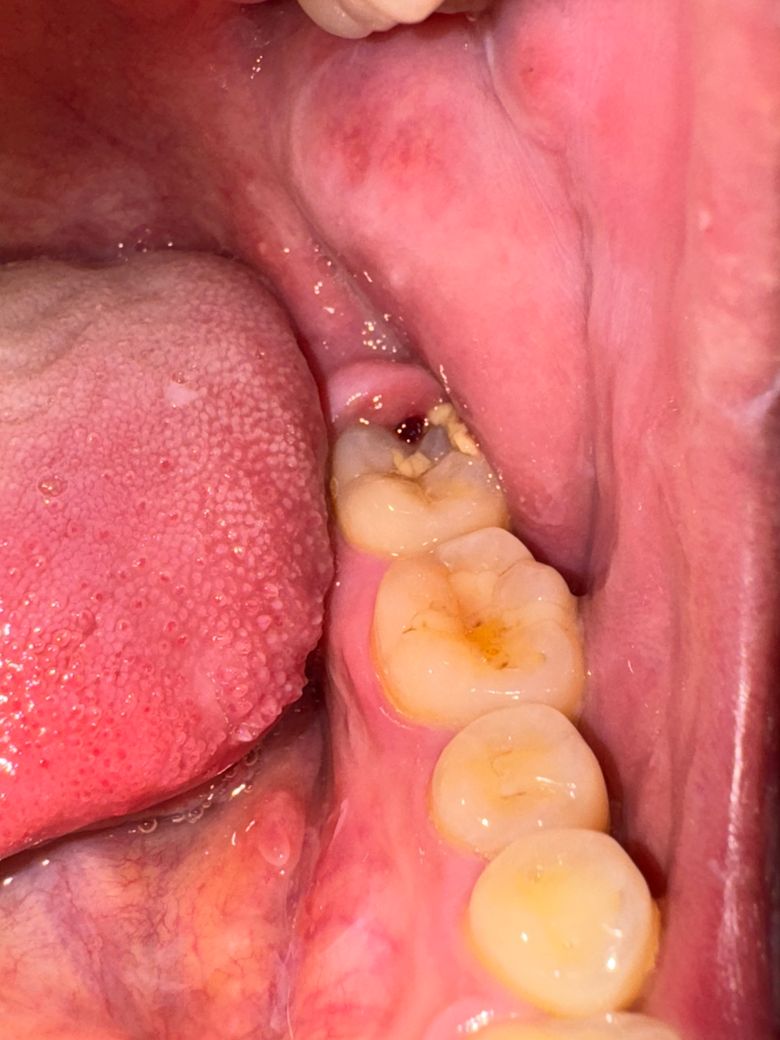

새벽에 통증있어서 일어나면 괜찮겠지 하고 겨우 잠들었는데 일어나자마자 욱씬거림이 더 심해져서 바로 사진찍은 모습입니다 주말이라 병원이 닫았는데 급하게 치과를 가야하나요 ?55글자 더 채워주세요.

바로 치과 가보시는 게 좋아보입니다. 염증과 충치가 모두 많이 진행된 것으로 판단됩니다.

충치가 많이 진행된 상태 같으니 치과에 가셔서 검진후 신경치료를 하셔야될수도 잇을것같습니다.

사랑니 부근 염증이 심해지신 것으로 보입니다. 아직 볼이나 턱 아래가 붓지 않았고 소염진통제로 어느정도 통증조절이 된다면 약 복용하시고 월요일에 가셔도 괜찮긴 합니다. 다만 음주나 흡연은 절대 금하시고 오늘 하루만이라도 푹 쉬셔야합니다. 혹여 열이나고 볼쪽이 부어오른다는 느낌이 들면 바로 치과나 응급실에 내원하셔야합니다.

현재 염증이 있는 것으로 보이며, 통증이 점점더 심해지는 경우에는 치과에 방문을 하는 것이 좋으며, 오늘 방문이 어려운 경우 우선 소독용 헥사메딘 가글액으로 가글을 하고, 소염진통제를 복용하는 것을 권합니다.